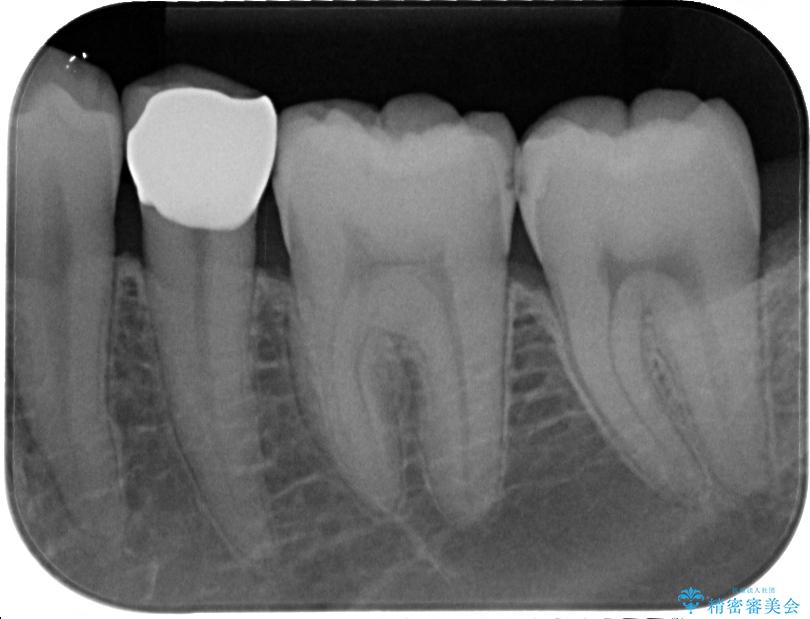

- 左下の奥歯のところがフロスが引っかかったり、ちぎれたりするとのことで来院された患者様です。検査の結果、神経は正常な反応を示し、フロスは引っかかる状態でしたので、虫歯治療も併せて行うためにオールセラミッククラウンによる補綴治療を行っていくことにしました。

拡大鏡視野下でプラスチックの詰め物、虫歯を除去しオールセラミッククラウンに適した形に整えました。